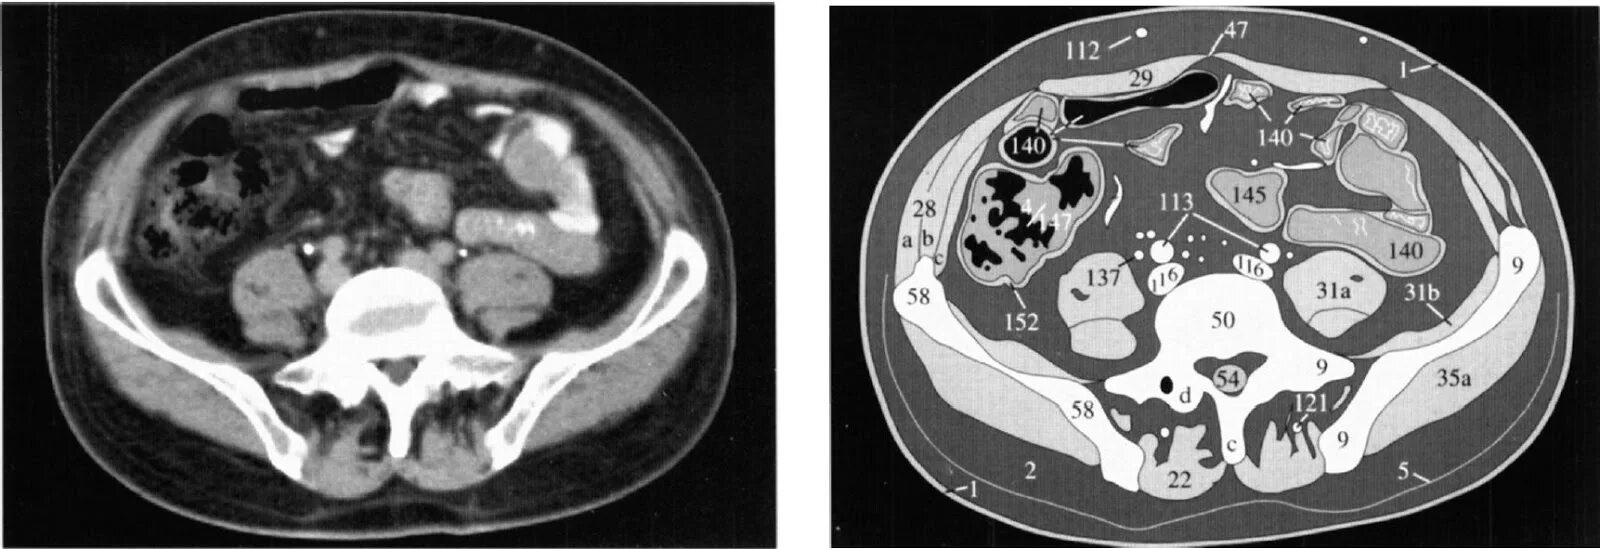

Кт брюшной полости краснодар